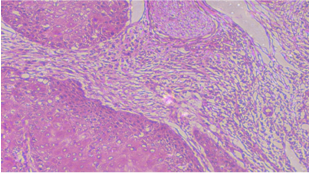

Histopathology of OSCC (Oral Squamous Cell Carcinoma) samples was done to grade them according to their differentiation. Histopathology was not only done to grade the tumor tissues but also used to get an idea about the prognosis or aggressiveness of disease. For histopathological grading of cases, 50-60 mg of OSCC (Oral Squamous Cell Carcinoma) tissue samples is obtained and put in formal saline. Parts were first embedded in paraffin wax; then tissue blocks were created and sliced into thin, uniformly cut sections using a microtome. The pieces were then placed on slides and stained with hematoxylin and eosin (fig. 1).

All the OSCC (Oral Squamous Cell Carcinoma) patients were graded clinicopathologically and histopathologically in various categories to keep an estimate about the aggressiveness and prognosis of the patient. Patients were histopathologically graded according to their differentiation into Well-differentiated tumors, i.e. Grade I and Moderately and poorly differentiated tumors, i.e., Grade II and we found that a little more than half of the patients recruited were in Grade I. Majority of tumors were located on the buccal mucosa (63.5%), 32% were located on tongue and only 9% were found on upper and lower gingival crevices. Around 80% of the patients were in early stages of OSCC (Oral Squamous Cell Carcinoma) with little or no lymph node involvement and rarely, we found any cases with distant metastasis (table 1, fig. 1A-D).

Fig. 1C: Poorly differentiated oral squamous cell carcinoma

Poorly differentiated tumors are defined by cellular dissemination, tumor stroma results from conversion of covering epithelium into stroma. This provides nitrition to tumor cells to grow and divide.

Fig. 1D: Verrucous carcinoma

Verrucous carcinoma a slow-growing tumor which is defined by the presence of rete ridges. It shows good prognosis.